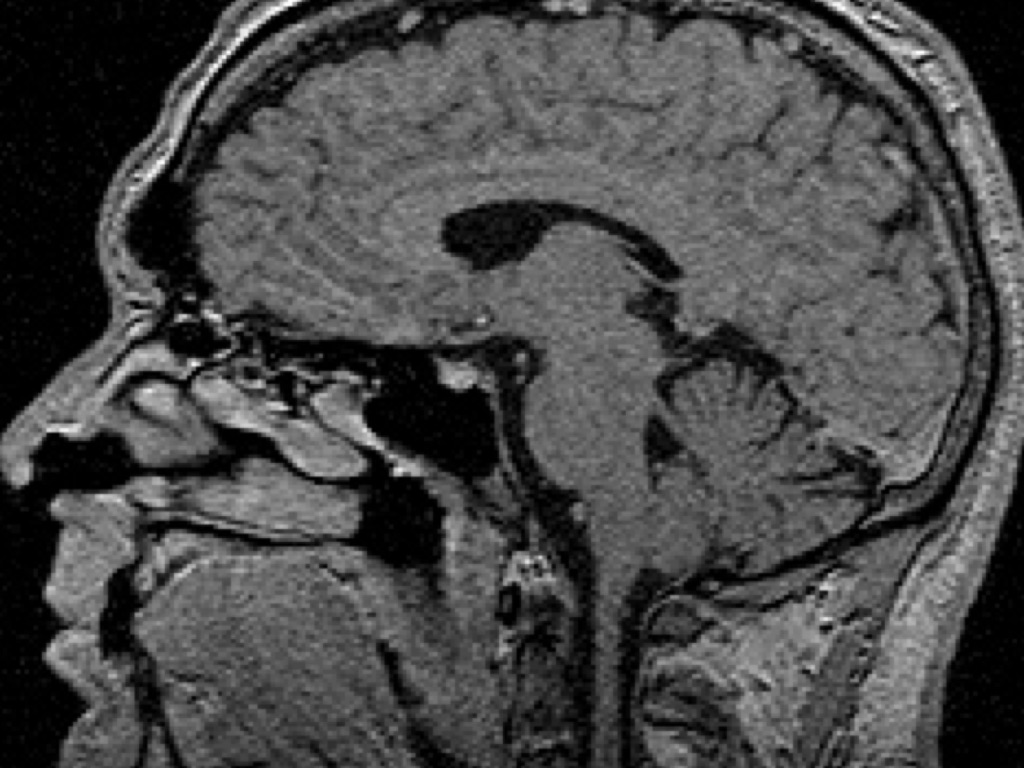

CRANIAL CT SCAN

RECOMMENDED TO HELP DIAGNOSE OR MONITOR:

• Birth (congenital) defect of the head or brain

• Brain infection

• Brain tumor

• Buildup of fluid inside the skull (hydrocephalus)

• Craniosynostosis

• Injury to the head and face

• Stroke or bleeding in the brain

A CRANIAL CT MAY ALSO BE DONE IF THERE IS...

• Sudden changes in thinking or behavior

• Symptoms of damage to part of the brain(vision problems, muscle weakness, numbness, etc...

• Fainting